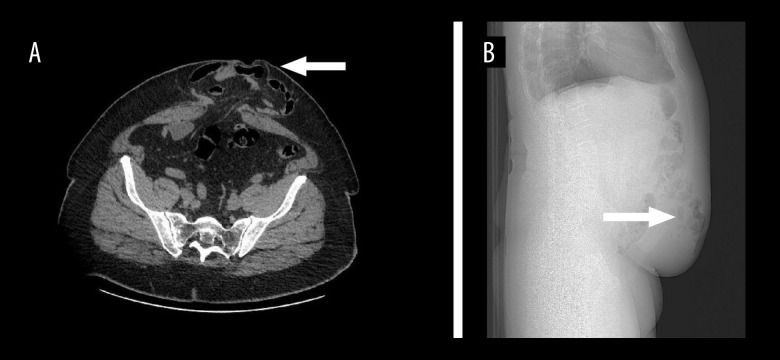

BACKGROUND Erector spinae plane block is a reliable and efficient analgesic method that can be used when alternatives are ineffective or impractical, and is a possible alternative to epidural anesthesia. This case report details the effective implementation of a continuous bilateral erector spinae plane block in a post-laparotomy patient, addressing the clinical complexities associated with the patient's polymorbidity and, notably, the main challenge of reinitiating anticoagulants postoperatively. CASE REPORT A 64-year-old man was scheduled for a major anterior abdominal wall hernioplasty. The surgery revealed severe complications from the previous hernioplasty, necessitating intestinal resection, and because of the ischemic changes in the sigmoid colon, a sigmoid resection with the creation of anastomoses was performed in addition to the scheduled hernioplasty. After the surgery, the patient was transferred to the Intensive Care Unit (ICU), with severe postoperative pain. Two catheters were placed bilaterally at the Th11 level for erector spinae plane blockade, and a 0.125% bupivacaine infusion was initiated at a rate of 5 ml/h. Despite the need for immediate application of anticoagulants due to the comorbidities of the patient, no complications associated with catheters occurred during the postoperative period. CONCLUSIONS The use of a prolonged ESP block with bilateral catheter insertion is a reliable and efficient approach for providing long-term pain relief in patients following extensive abdominal surgery.